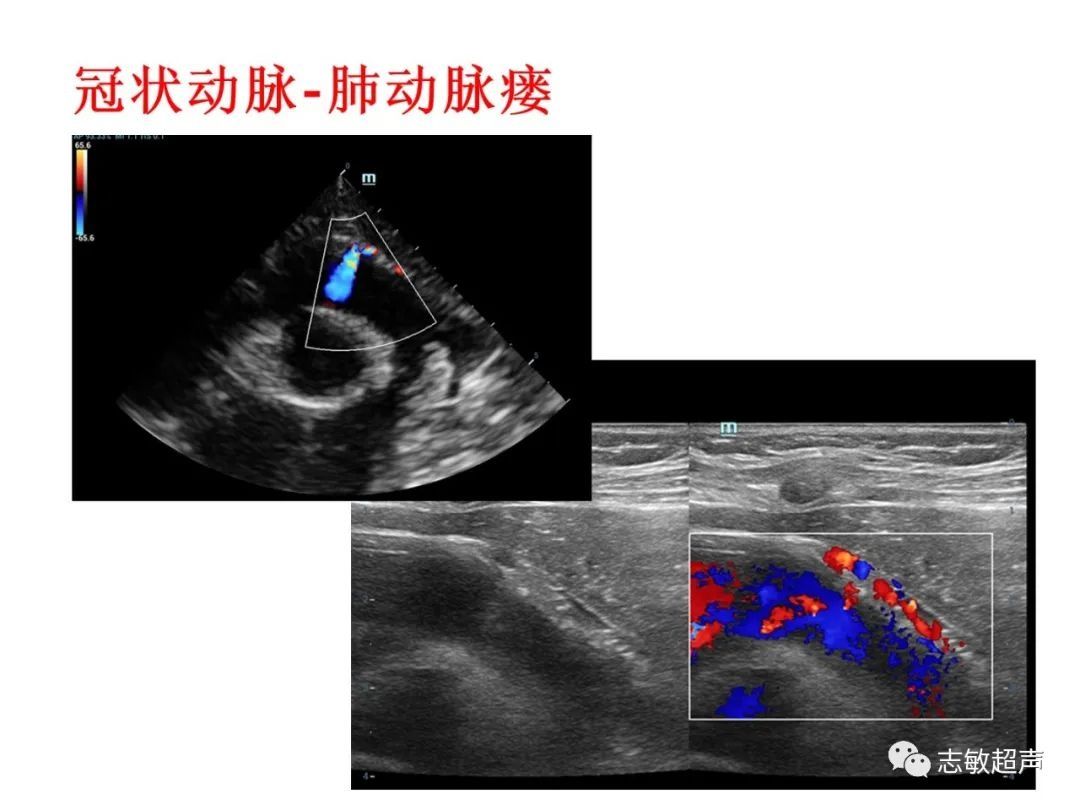

4.冠状动脉肺动脉瘘

冠状动脉-肺动脉瘘视频